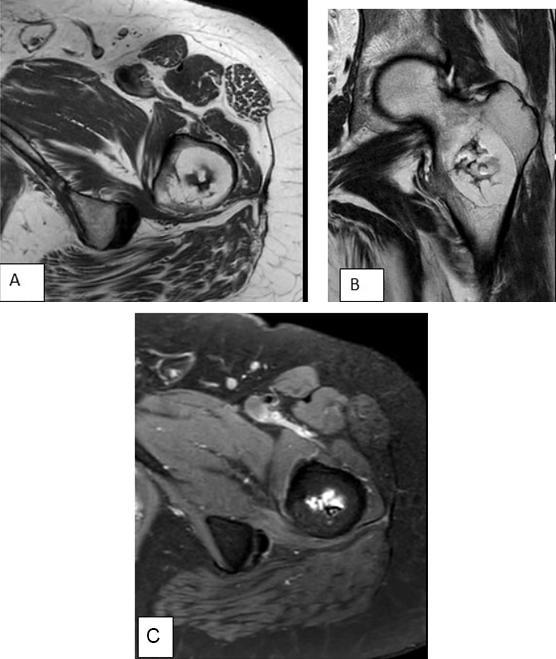

For further study, an MRI of the left hip was performed, axial MRI, T1-weighted (A), coronal T2-weighted (B), and axial T2-weighted images with fat suppression (C) showed in the intertrochanteric region of the proximal femur a hyperintense signal in the periphery’s lesion on T1-T2 weighted images, suppressed in the short tau inversion recovery (STIR) sequence corresponding to the fat, while the central part contains a space filled with fluid (low on T1, high on T2) and irregular internal low-signal-intensity area corresponding to dystrophic calcification (Figure 3). Based on the MRI results, the intraosseous lipoma was confirmed, and no other investigations were required.

Figure 3: Axial MRI, T1-weighted (A), coronal T2-weighted (B), and axial T2-weighted images with fat suppression (C), showed in a lesion of the intertrochanteric region of the proximal femur with a peripheral hyperintense signal on T1-T2 weighted images, supressed on the STIR sequence corresponding to the fat. The central part contains a fluid filled space (low on T1, high on T2) and irregular hypointense area corresponding to dystrophic calcification.

Regarding the case of this study, it is a stage 3 intraosseous lipoma since the lesion contains fat, dystrophic calcification as well as cystic spaces. The etiology of intraosseous lipoma is unknown; many theories were considered: a secondary posttraumatic bone reaction; fatty bone infarct with metaplasia; infection and tumor etiology because it is a benign tumor [5],[6].

The CT scan demonstration of intraosseous lipomas consists of a lytic lesion with distinct borders and a negative Hounsfield unit parallel to the adipose tissue. While irregularity of the bone cortex and marginal sclerosis surrounding the lesion are commonly observed [10]. Intraosseous lipoma presents on MRI as a lesion with a high signal intensity lesion on both T1 and T2-weighted images identical to that of adipose tissue that allows differentiation from other bone lesions [10].

In the present case, the hyperintense signal on the T1 and T2 weighted images as well as the decrease in the signal in the fat removal image allowed the distinction between intraosseous lipoma and other bone lesions.